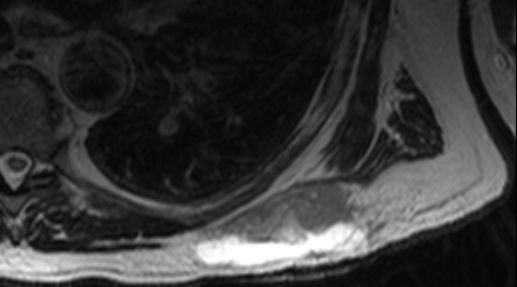

| Oberschenkel | 49-jährige Frau mit einem myxoiden Liposarkom der rechten Adduktoren-Loge.![]() |

Die enge Lagebeziehung zur A. femoralis ist gut erkennbar.![]() ![]() |